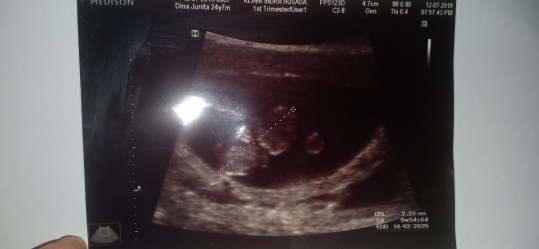

Hamil usia 9 minggu

Saya hamil udah 9 minggu kemarin baru saya cek ke bidan dan di situ sama bidan di usg tapi kok belum kelihatan itu normal gak sih bunda?? Tolong dong yang sudah berpengalaman share ke saya. Terimakasih bunda

sya kmrin 9w udh keliatan bun pke yg 2d. cba bunda ke spog aja. tkutnya pas di usg kmrin dedenya ngumpet. krna msh kecil pling 2cm lebih ukurannya

Coba kdokter aja bun. Hrsnya 9w udah ada sih

saya 8w udah bun, coba ke dr spog aja bun